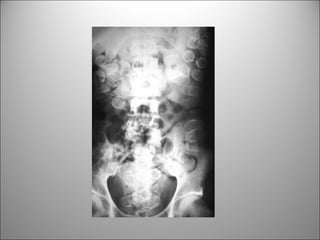

PATRÓN DE GAS INTESTINAL

• Contraste natural

• Puedo diferenciar entre Int. delgado y cólon?

– Si, principalmente si hay distensión

Dato clave:

REGLA DEL 3/6/9

3 cm Int. Delgado

6 cm Colon

9 cm Ciego

EL COLON

• Taenia coli + musc. Circulares  haustras

•Posición periférica

• Transverso y

sigmoides posición

variable

• Haustras

• Heces